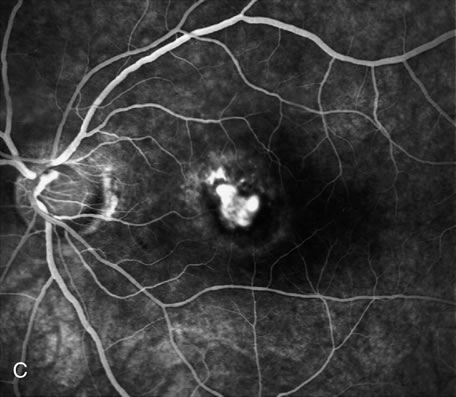

FA is generally not necessary to make the diagnosis of cystoid macular edema (CME). A history of recent cataract surgery, diabetes, uveitis, or other predisposing conditions is usually obtained. Clinically, the patient presents with retinal thickening, often with clinically evident cystic changes. FA reveals a characteristic petaloid collection of fluorescein that confirms the diagnosis, which has been shown histologically to reflect accumulation of fluid in the extravascular component of the outer plexiform layer.239 When FA demonstrates leakage from the optic nerve, this suggests an inflammatory etiology for the CME (Fig. 36). Although this sign is reliably present in CME associated with cataract surgery, penetrating keratoplasty, or posterior uveitis, it is not characteristically present in diabetics or in idiopathic CME. FA can also demonstrate dilated macular capillaries as a cause of CME in diabetes (Fig. 37). Different conditions that may cause CME include Irvine-Gass syndrome, previous penetrating keratoplasty, any inflammatory condition that involves the posterior segment, peripheral rhegmatogenous retinal detachment, peripheral cryotherapy, malignant melanoma, topical epinephrine, tapetoretinal degenerations, juxtafoveal telangiectasia, occult central retinal vein occlusion, nicotinic acid maculopathy, and idiopathic CME.

Fig. 36. Cystoid macular edema (CME). This patient had bilateral vitritis and CME. A. Early-phase photograph of the right eye reveals telangiectasia of the perifoveal retinal capillaries with some early leakage visible temporally. B. Mid-phase photograph of the left eye reveals more intense fluorescence leakage. C. Late-phase photograph of the left eye demonstrates cystic accumulation of fluorescein in a classic “petaloid” configuration. The late-phase staining of the optic nerve head in this fluorescein angiogram suggests an inflammatory cause of the CME.